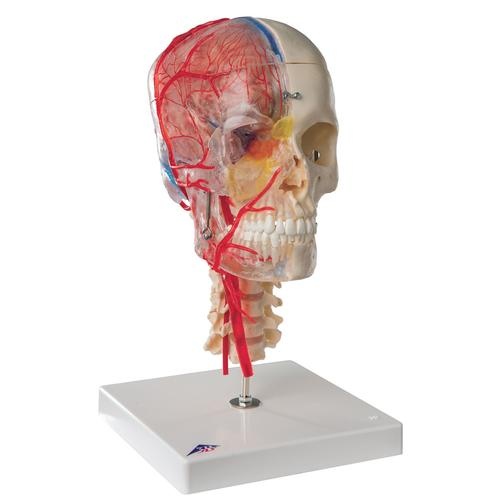

Flexibel montierte Abformung der menschlichen Wirbelsäule in hervorragender BONElikeTM Qualität

mit originalgetreuer Wiedergabe aller anatomischen Details und realem Gewicht.

Mit männlichem Becken und Hinterhauptschuppe.

Hinterhauptschuppe und Atlas sind einzeln abnehmbar.